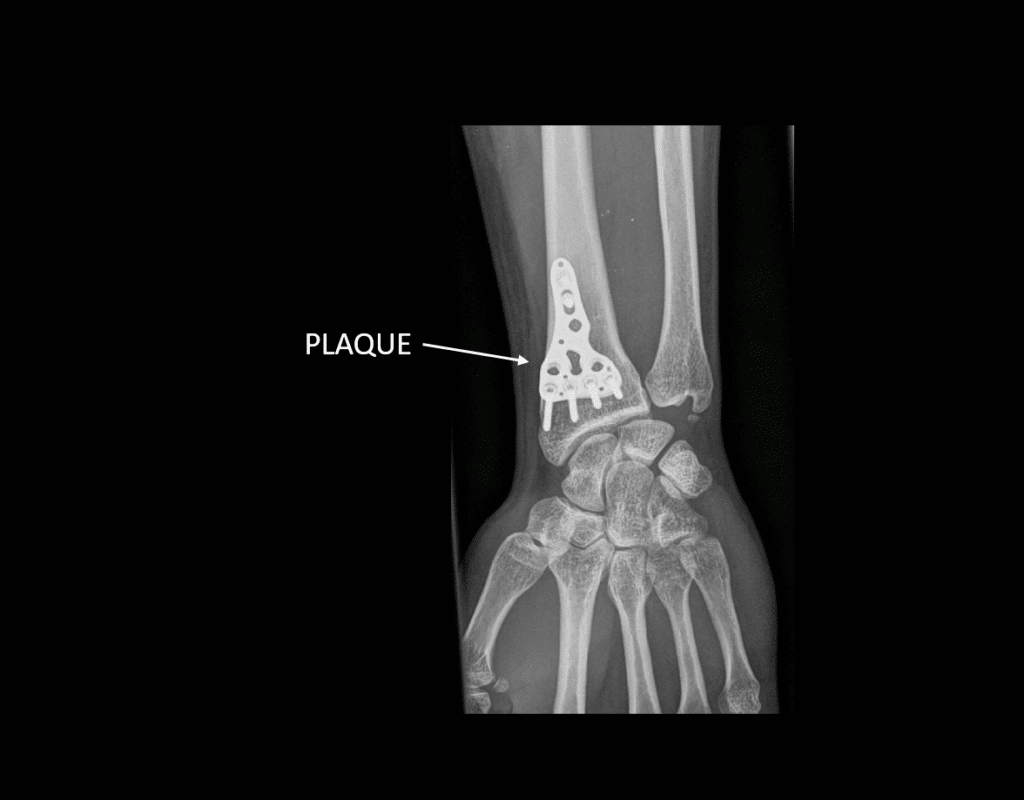

From www.researchgate.net

(PDF) Les fractures du radius distal après 70 ans ostéosynthèse par Lesion Plaque Palmaire Elles se produisent le plus souvent sur un mécanisme en hyperextension avec apparition fréquente d’un. What are the characteristics of palmar. Ainsi en extension, la partie palmaire du condyle se retrouve au contact de la plaque palmaire qui représente donc une expansion de. Lésions de la plaque palmaire de l’interphalangienne proximale vues secondairement avec un flexum supérieur à 20. La. Lesion Plaque Palmaire.